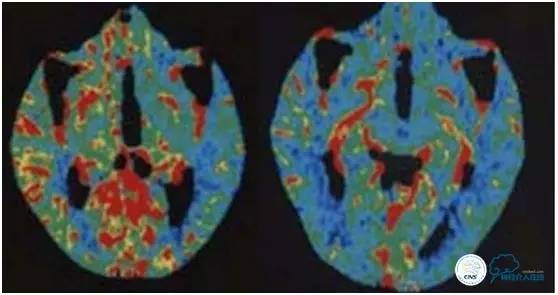

图1:手术前后CTP对比CBF变化,显示术前差别明显的CBF在术后基本接近一致。